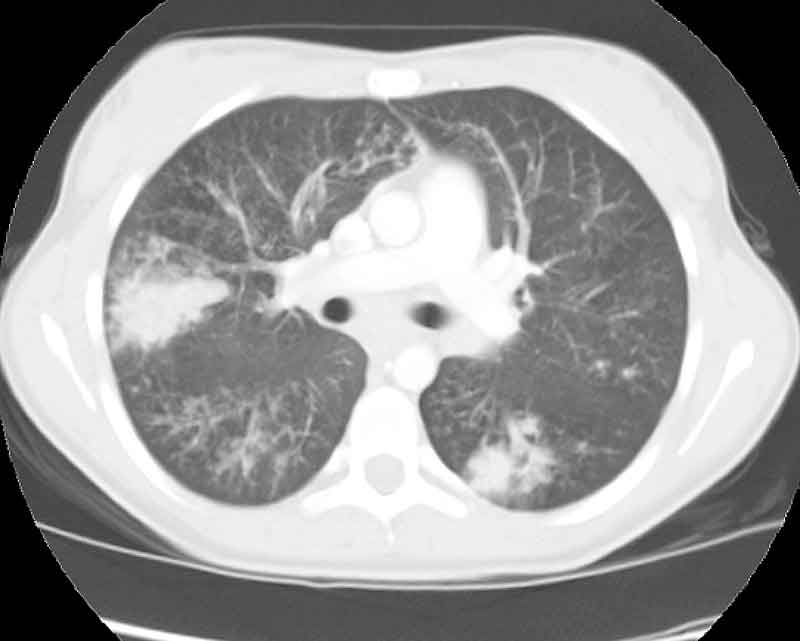

Below are selected CT images from June 2003

CT #15

(ENLARGE CT #15)

CT #20 (ENLARGE

CT#20)

CT #22 (ENLARGE

CT #22)

WHAT IS YOUR INTERPRETATION OF THESE XRAYS?